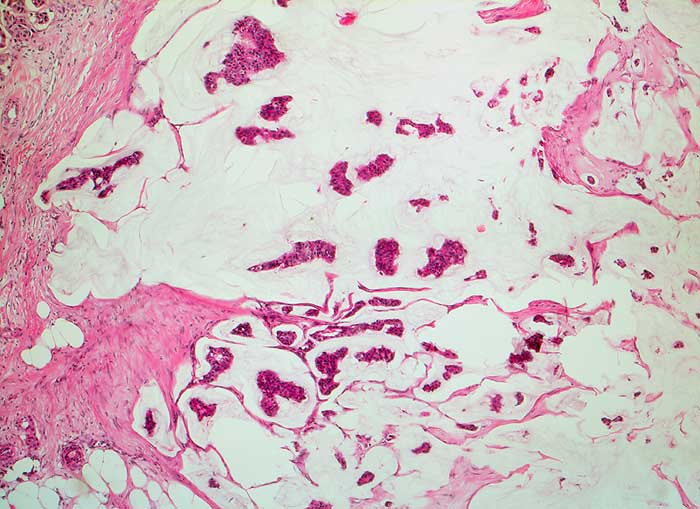

muzinöses Mammakarzinom

Schleimseen mit inselförmigen Tumorzellverbänden umgeben von Bindegewebssepten.

Karzinomrezidiv parasternal links nach Mastektomie

Zytologische Diagnose: muzinöses Karzinom

Histologie

50